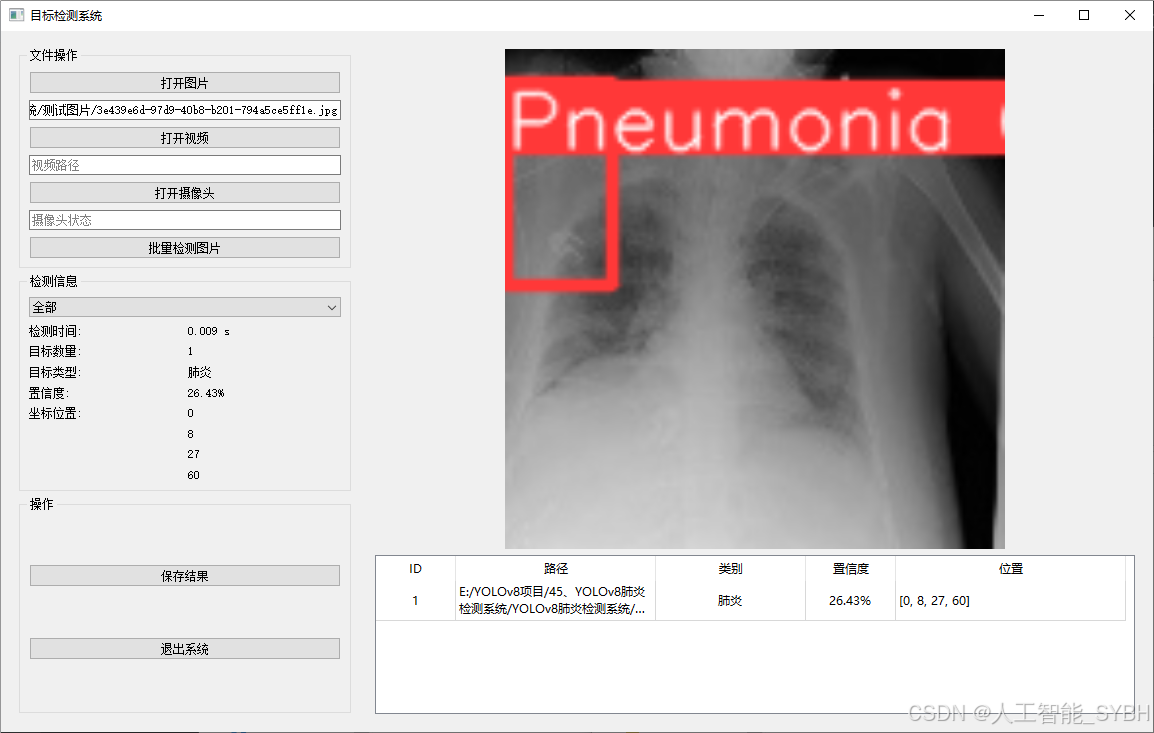

二、项目功能展示

系统功能

✅ 图片检测:可对单张图片进行检测,返回检测框及类别信息。

图片检测

该功能允许用户通过单张图片进行目标检测。输入一张图片后,YOLO模型会实时分析图像,识别出其中的目标,并在图像中框出检测到的目标,输出带有目标框的图像。批量图片检测